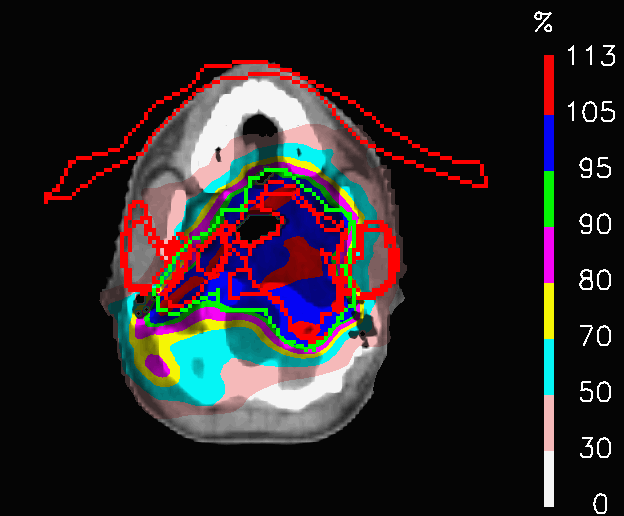

The OL penalization is, here, exploited to switch off the fields in selected areas and to test a new field geometry. In PLAN-OL-1, two artificial VOIs were drawn at the level if the shoulders and were assigned with OL = 1, to switch off, respectively, the posterior fields irradiating that area. In PLAN-OL-2, two addional artificial VOIs are created at the level of the head and set with OL = 1, to switch off the anteriori fields in the part of the patient volume and a fifth intra-cranial field is added to compensate for the target coverage, as shown in Fig.6.

Refer to caption

Figure 6: Head and neck tumour: azimuthal CT slice showing the fifth intracranial field added for PLAN-OL-2.

In PLAN-OL-2, a different field geometry has been investigated: the posterior fields are switched off at the level of the shoulders, the anterior ones at the level of the head and a fifth intracranial field is added (Fig.6). The goal was to achieve a better preservation of the OARs inside the head. The dose distributions (Fig.16) share a very similar coverage of the target volume, but they are characterized by substantial differences in the dose delivered to the OARs, as shown by Table 5. In fact, the huge improvements in the sparing of the chiasm, right lens (Fig.17a), left lens (17b), left inner ear and the spinal cord (considering in first place the decrease of 𝐃𝐦𝐚𝐱subscript𝐃𝐦𝐚𝐱\mathbf{D_{max}}) are followed by a significant increase of the peak dose inside the thyroid and the mean dose to the brainstem. In this case, PLAN-OL-2 is not necessarily superior to PLAN-NOM, but it is undeniable that the OL penalization has allowed the planner to test a scenario, that the simple enforcement of the dose constraints would not have provided.